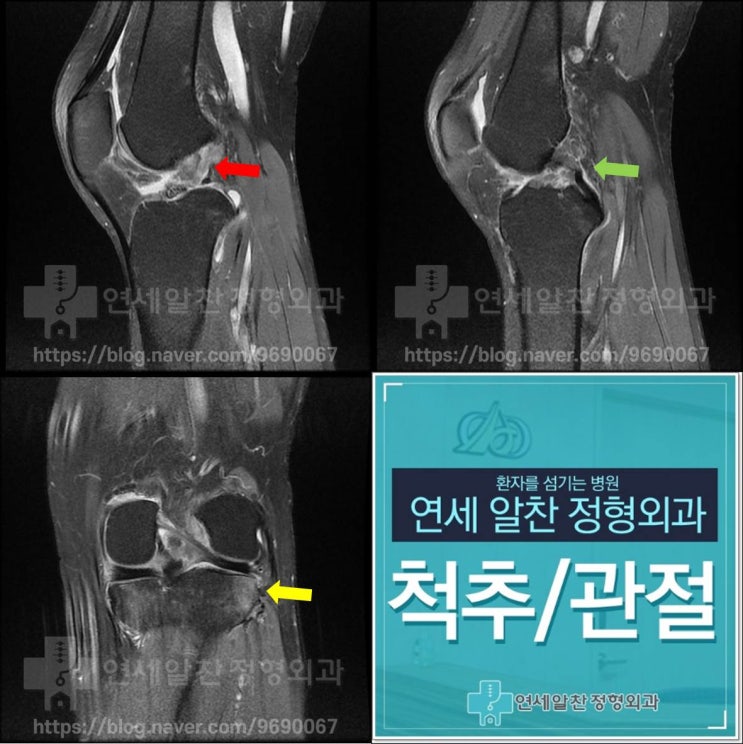

슬관절 통증의 진단에서 history taking, 이학적 검사의 중요성

50세 여자환자가 무릎 통증을 주소로 내원하였다. 환자는 2개월전 턱에 걸려 넘어지면서 무릎이 꺽이면서 ...